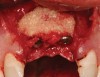

Figure 15  After extraction and 3 months of healing, two implants were placed in ideal position and with primary stability at sites Nos. 8 and 9. Implants were stable. Dehiscence defects exposing 13 threads were produced.

Figure 15